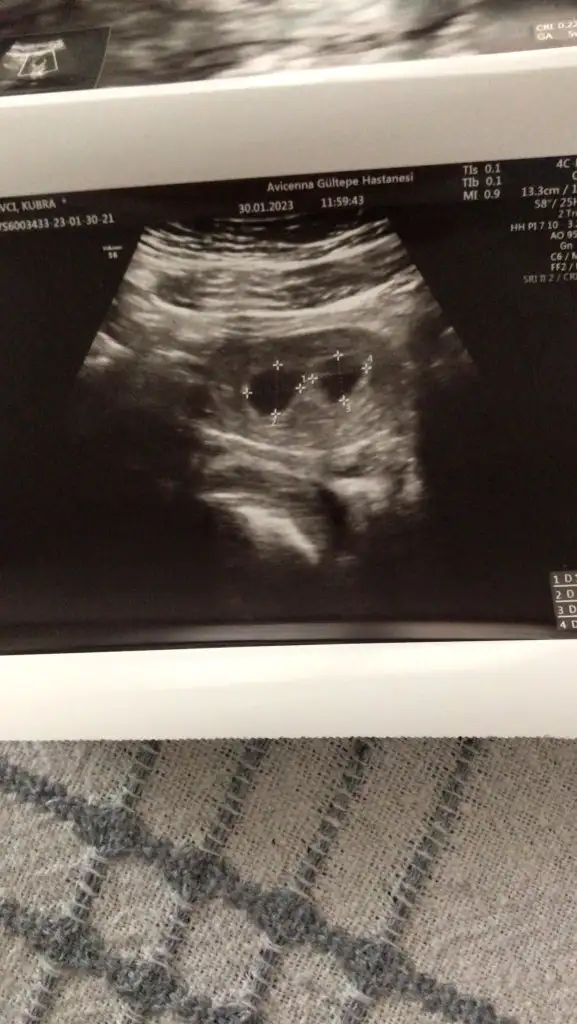

6+0 yazıyor gördüm tamam çok güzel maşallahEkte canım benim attım

Bana 5+5 dedi doktor6+0 yazıyor gördüm tamam çok güzel maşallah

Öyleymiş tamam cnm yanlış görmüşüm ben hayırlı olsunBana 5+5 dedi doktor